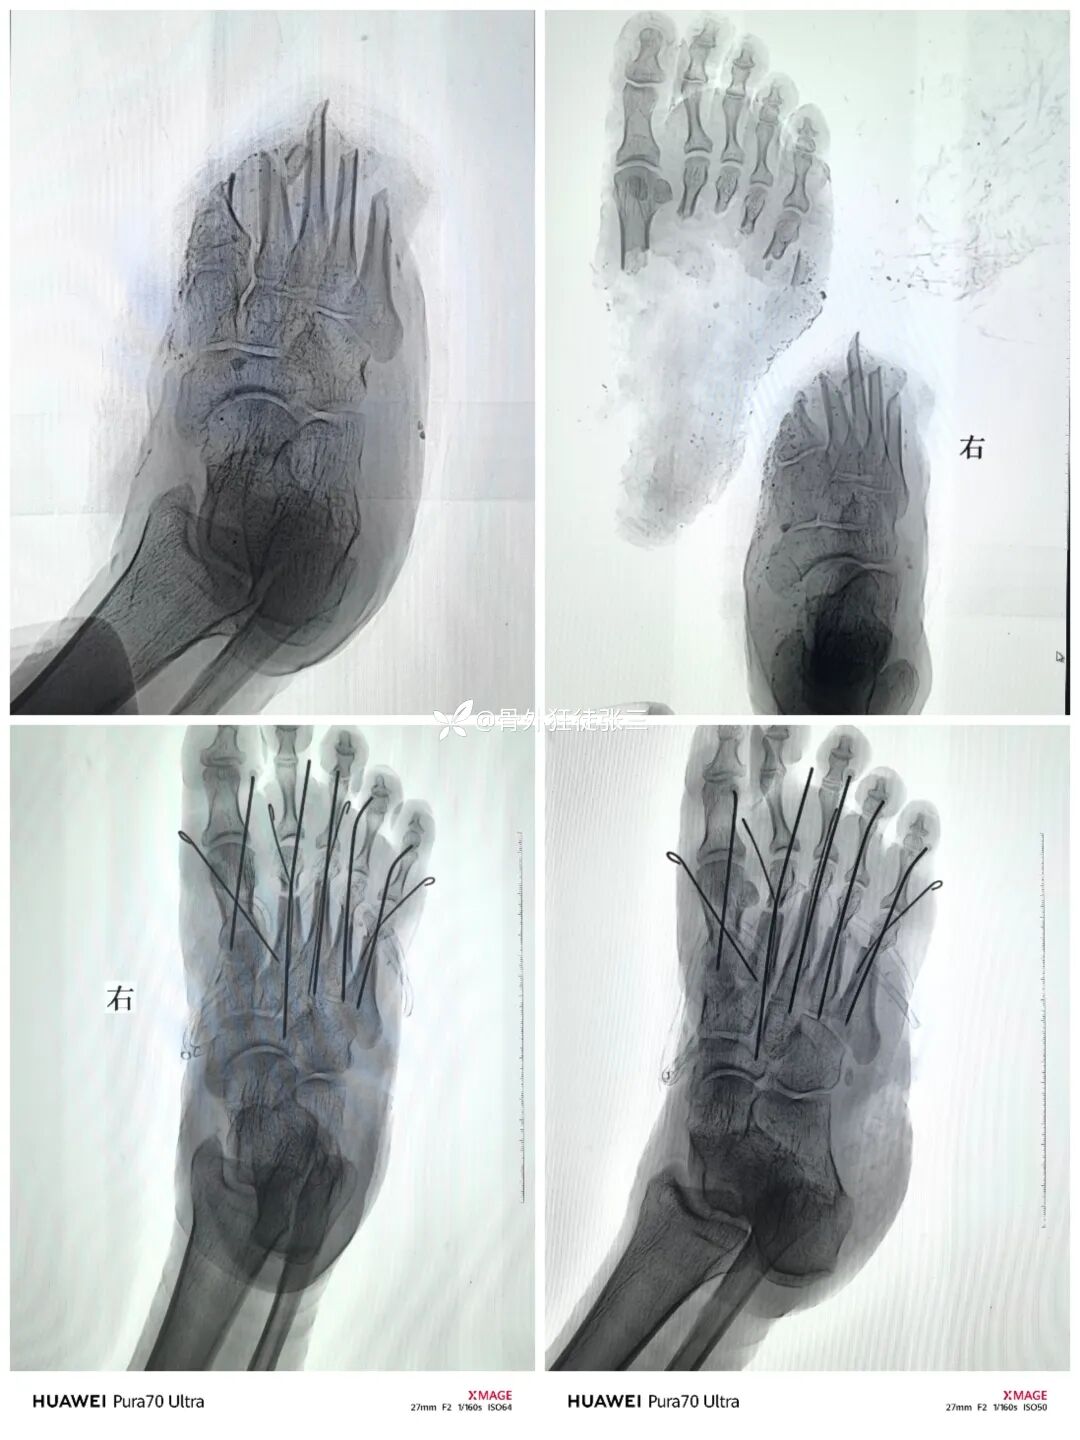

跖骨骨折常伴严重软组织损伤,治疗需兼顾骨性稳定与软组织保护。逆行髓内克氏针技术以微创方式实现有效内固定,尤其适用于多发骨折、开放损伤或软组织条件差的患者。其操作简便、血运破坏少,在损伤控制中展现独特优势。本文通过四例典型病例,探讨该技术在闭合性、开放性及严重毁损伤中的临床应用价值。

闭合性2-5跖骨骨折

逆行髓内针